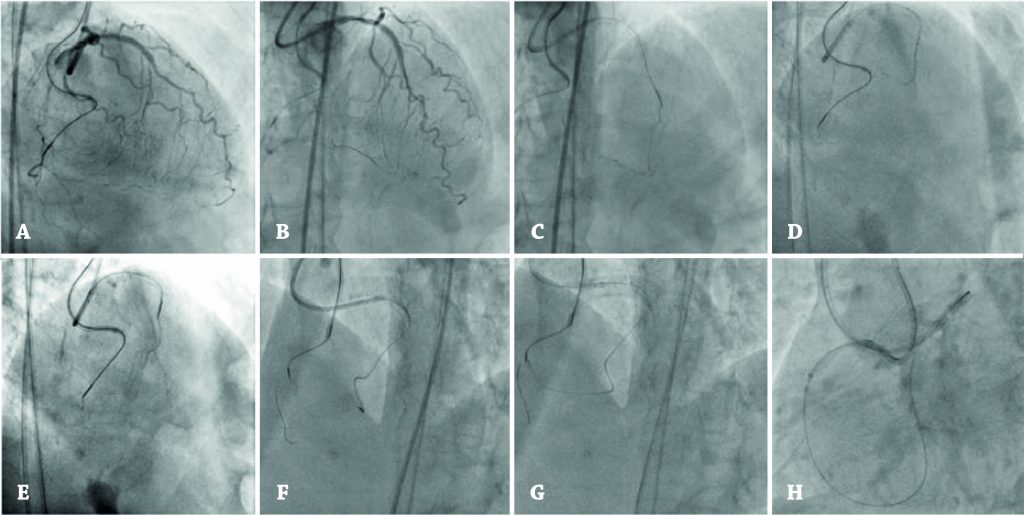

Técnica retrógrada para tratamento percutâneo das oclusões coronárias crônicas

As oclusões coronárias crônicas são diagnosticadas em cerca de 20% das coronariografias, mas a recanalização percutânea dessas lesões é subindicada. Esses pacientes são usualmente tratados com revascularização percutânea incompleta ou referenciados para cirurgia de revascularização miocárdica. O constante avanço nos dispositivos de intervenção, associado a técnicas inovadoras, propiciou importante incremento nas taxas de sucesso de recanalização, mesmo nos cenários anatômicos mais complexos. As técnicas de abordagem retrógada são consideradas parte do conjunto de habilidades essenciais para um operador dedicado a oclusões coronárias crônicas e provavelmente a etapa mais difícil do treinamento. Refinamentos da técnica retrógrada foram essenciais para alcançar os padrões de sucesso e segurança atuais. Os autores propõem um guia passo a passo para os operadores interessados em adotar essa estratégia.